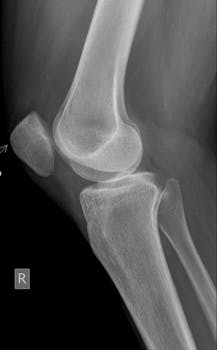

The Lachman examination is a critical component of knee assessments and is often used by healthcare professionals to evaluate the integrity of the anterior cruciate ligament (ACL). Understanding this examination can aid in diagnosing ACL injuries accurately, which is important for athletic individuals and those experiencing knee instability. This article will explore the Lachman exam in detail, provide guidance on its execution, and highlight its significance in sports medicine.

The Lachman examination is a physical test performed to assess the ACL’s condition. The ACL is crucial for stabilizing the knee joint, and damage to it can severely impact mobility and function. Clinicians often perform this test when an ACL injury is suspected due to trauma or sports-related activities. The Lachman test is recognized for its sensitivity and accuracy compared to other diagnostic methods like the anterior drawer test.

The Lachman exam requires the patient to lie on their back with their knees bent at approximately a 30-degree angle. The examiner stabilizes the patient’s thigh with one hand while the other hand gently displaces the tibia forward. The goal is to feel for excessive forward movement or a “soft endpoint,” which may indicate an ACL tear.